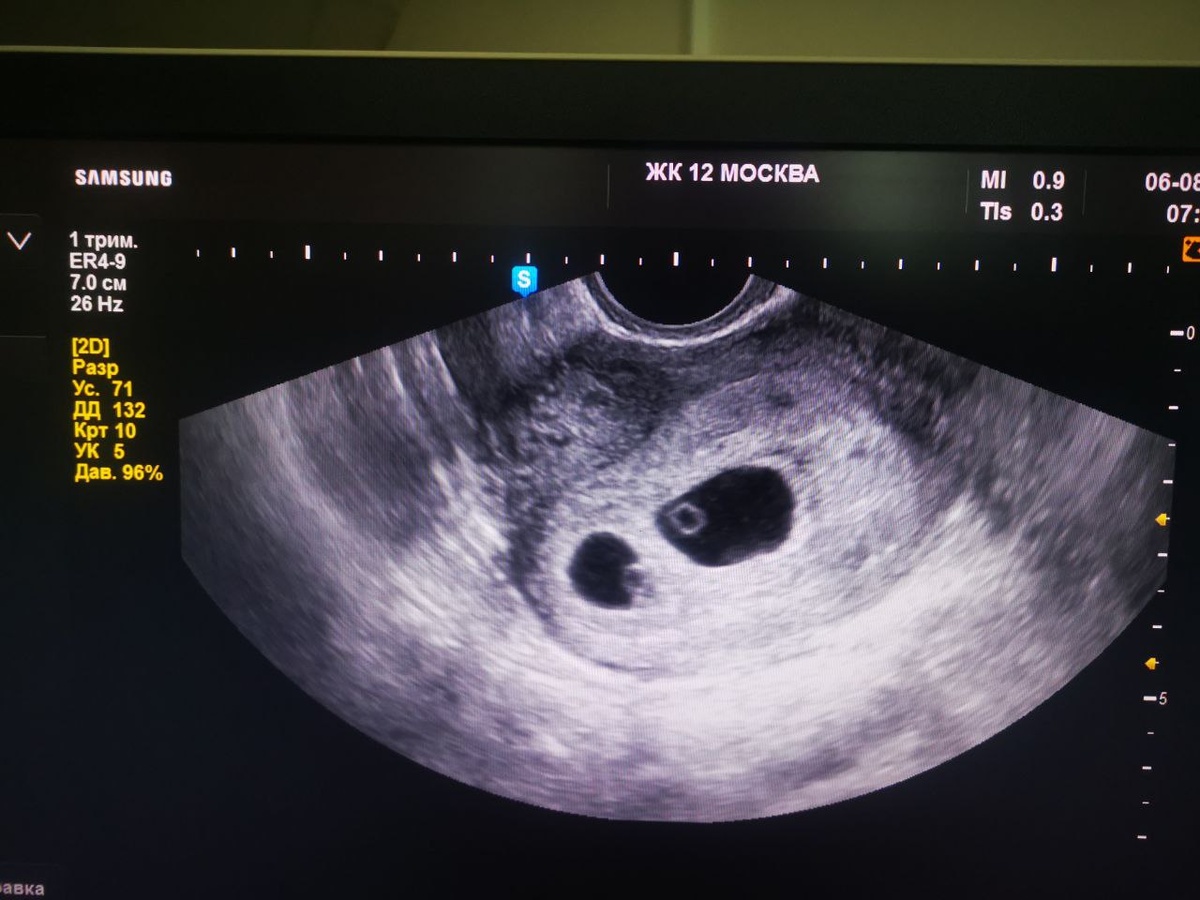

Мне не нужна фальшивая поддержка. Нужны те, кто знает, как пахнет страх перед родами, когда их ждёшь не для себя, а для двоих. Кто помнит, как смотрел на УЗИ и не радовался, а считал: «Сколько это будет стоить? Где мы будем спать? Кто я для них — мать или просто машина для выживания?»

И вдруг — эти слова: «У вас будет двойня».